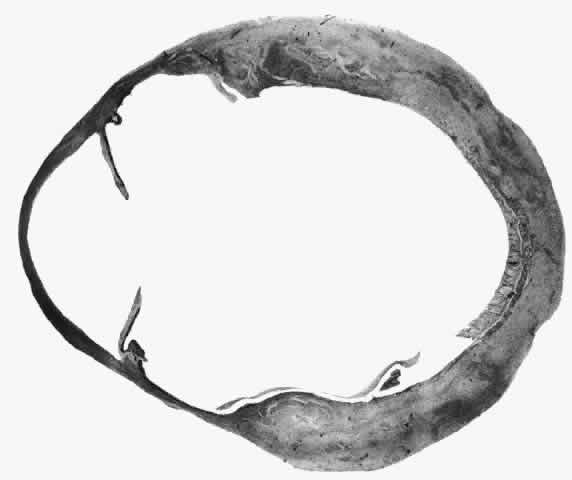

Scleritis usually affects the anterior segment of the eye, possibly because this is the area with the best blood supply, but with sluggish flow through the vessels (Fig. 19). The sclera is thickened and roughened in the affected area, which appears to be sharply demarcated from the rest of the sclera. However, tissue obtained at surgery during the course of grafting of areas adjacent to necrotic tissue shows marked pathologic changes.20,21 The area of affected sclera may be swollen, excavated, or frankly ulcerated with undermined edges covered with a thin layer of fibrous tissue. However, spontaneous perforation is extremely unusual and, where seen in pathologic specimens, has usually occurred at the time of removal of the eye. A posterior scleritis often occurs as an extension of anterior disease; but, as in Figure 20, most of the inflammation (in some cases all of the inflammation) is in the posterior segment and the exudative detachments and subretinal granulomas can be mistaken for malignant melanoma.

Fig. 19. Anterior necrotizing scleritis. The eye was removed because of loss of vision and intractable pain. No form of steroid was given to this patient because of a severe Pseudomonas infection of the chest. (Courtesy of Professor N. Ashton)

Fig. 20. Posterior scleritis. This eye was removed because of loss of vision and pain, mistakenly diagnosed as malignant melanoma. (Courtesy of Professor N. Ashton)